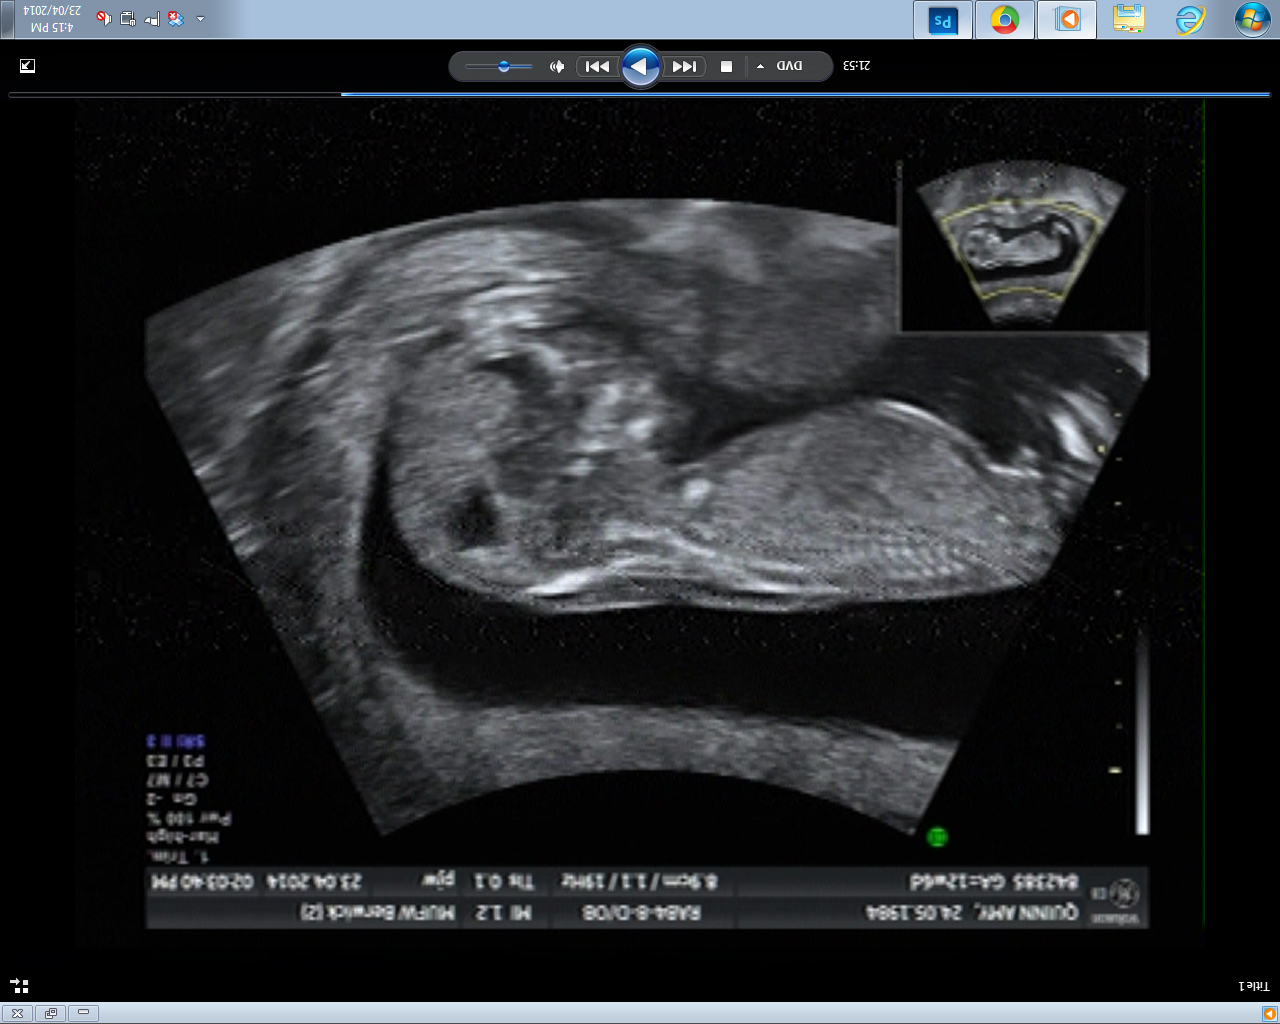

Potty shot 2 - bub has one heck of a full bladder. Just like Mummy...

Attachment 18367

...it's a boy, isn't it?